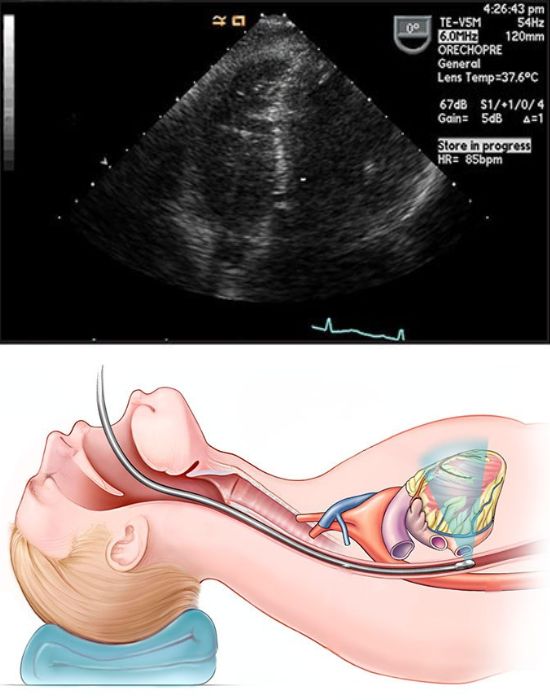

Трансезофагеальна ехокардіографія